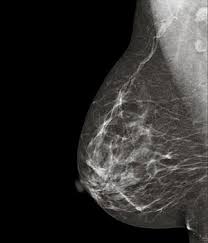

Alrededor de medio millón de mujeres andaluzas de entre 49 y 71 años acudimos cada año a nuestra sanidad pública para someternos a una mamografía. Cuando se obtienen los resultados de estas pruebas, muchas respiran aliviadas y olvidan, al menos durante un año, que el cáncer acecha, y, de hecho, al mismo tiempo que vuelven a sus vidas y a sus rutinas, desgraciadamente muchas otras madres, hijas, amigas, hermanas, abuelas descubren el vértigo infinito de un diagnóstico positivo. Se instalan en el desasosiego y sus familias y todos los que se preocupan por ellas las acompañan, hasta el final. Está cargado de años y sigue haciendo el camino …

Sucede en nuestra comunidad autónoma, nadie sabe desde cuándo, que si un año, que si dos, nadie sabe justo dónde, que si en la provincia de Cádiz, es decir, en nuestra provincia, que si en Sevilla, que si ya iremos viendo dónde más acontece, que para aquellas pruebas con diagnóstico dudoso, algo no funcionó como debiera. Porque cuando no se da un resultado concluyente en estas cribas, se requiere de una comprobación complementaria, y a todas estas mujeres a las que había que habérselas realizado para garantizarles el derecho 43 de nuestra Constitución Española que reconoce “el derecho a la protección de la salud”, nadie sabe cómo, nadie, se las ha dejado a la intemperie. Todas escucharon antes de abandonar alguno de nuestros centros sanitarios públicos que si algo fuese mal, que si alguien advirtiese algún riesgo, se las localizaría, se les haría saber. Algunas de ellas ya están, y, otras estarán muertas cuando se produzcan esos avisos. Nadie sabe cómo ha podido suceder. Al conocerse la situación, encontramos una respuesta de choque numérica disuasoria ante el desconcierto generalizado. Como mucho mucho, son, vamos a ver, son solo, unas, unas 2.000 y pico, vamos nada, un 0,4% del total de pruebas realizadas, que ahora parece ser que sí, que alguien sabe algo, vaya por Dios, más vale tarde que nunca, bien está lo que bien acaba, y para quien nunca supo, ojos que no ven corazón que no siente.  Y sigue haciendo el camino, aunque dice con tristeza “para el próximo no vivo”.